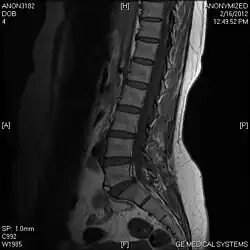

Limbus vertebra

A limbus vertebra is a bone tubercle formed by bone trauma on a vertebral body, bearing a radiographic similarity to a vertebral fracture. The anterior-superior corner of a single vertebra is the common site for this defect although it can also be seen at the inferior corner as well as the posterior or anterior margin. Anatomically, it is assumed to be an intra-vertebral body herniation of the disc material occurring during adolescent growth spurt when the ring apophysis has not yet fused. It was first described by Schmorl in 1927[1] and later in detail by Leif Sward and Adad Baranto.

Viewed in a lateral radiograph, it appears as a triangular shaped bone fragment, not unlike an anterior lip fracture, but with softer edges.

Limbus vertebra is not always symptomatic, but severe cases may lead to more serious pathological conditions and chronic pain. In rare instances, a posterior limbus vertebra has been described causing radiculopathy due to nerve root compression. [2]